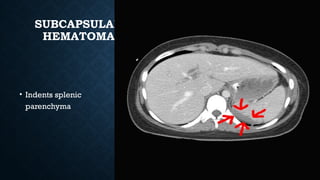

SUBCAPSULAR

HEMATOMA

• Indents splenic

parenchyma